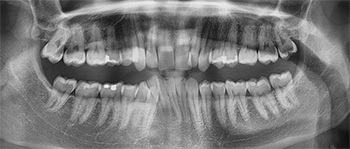

The patient, a 23-year-old member of the National Guard, wanted to get started with his treatment; however, he was scheduled for deployment from South Carolina to Arizona. After discussing his unique situation during the initial consultation (Figs. 1–4), we determined we could achieve the treatment goals with clear aligner treatment along with remote monitoring. This report details his successful results managed with minimal office visits.

Fig. 2

Initial records revealed:

• Class I malocclusion with posterior crossbite on the left

• Severe overbite

• Moderate overjet

• Moderate upper crowding

• Severe lower crowding

• Thin attached gingiva #27